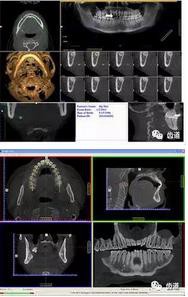

三)種植修復(fù)

CBCT在牙種植修復(fù)中的應(yīng)用。種植前利用CBCT對患者的牙床進(jìn)行檢查,可精準(zhǔn)判斷牙槽骨的寬度、厚度及高度、骨的密度、重要的顏面神經(jīng)、血管和鼻竇位置等。臨床醫(yī)生不僅可以在計(jì)算機(jī)直觀的看到牙槽骨的立體影像,還可以切換不同的視角來觀察硬組織之間的位置關(guān)系,在手術(shù)方案中避開危險(xiǎn)區(qū)域,保證手術(shù)的安全性。臨床醫(yī)生還可以利用CT數(shù)據(jù)進(jìn)行數(shù)字模型重建,配合軟件預(yù)先做好手術(shù)模板,使種植手術(shù)更安全快捷,避免在種植手術(shù)過程中不慎破壞神經(jīng)、鼻竇等解剖結(jié)構(gòu),導(dǎo)致顏面神經(jīng)麻痹、鼻竇炎等并發(fā)癥的發(fā)生。

1、下頜骨種植牙前測量準(zhǔn)備影像

2、上頜骨種植牙前準(zhǔn)備影像

3、下頜骨種植牙術(shù)后